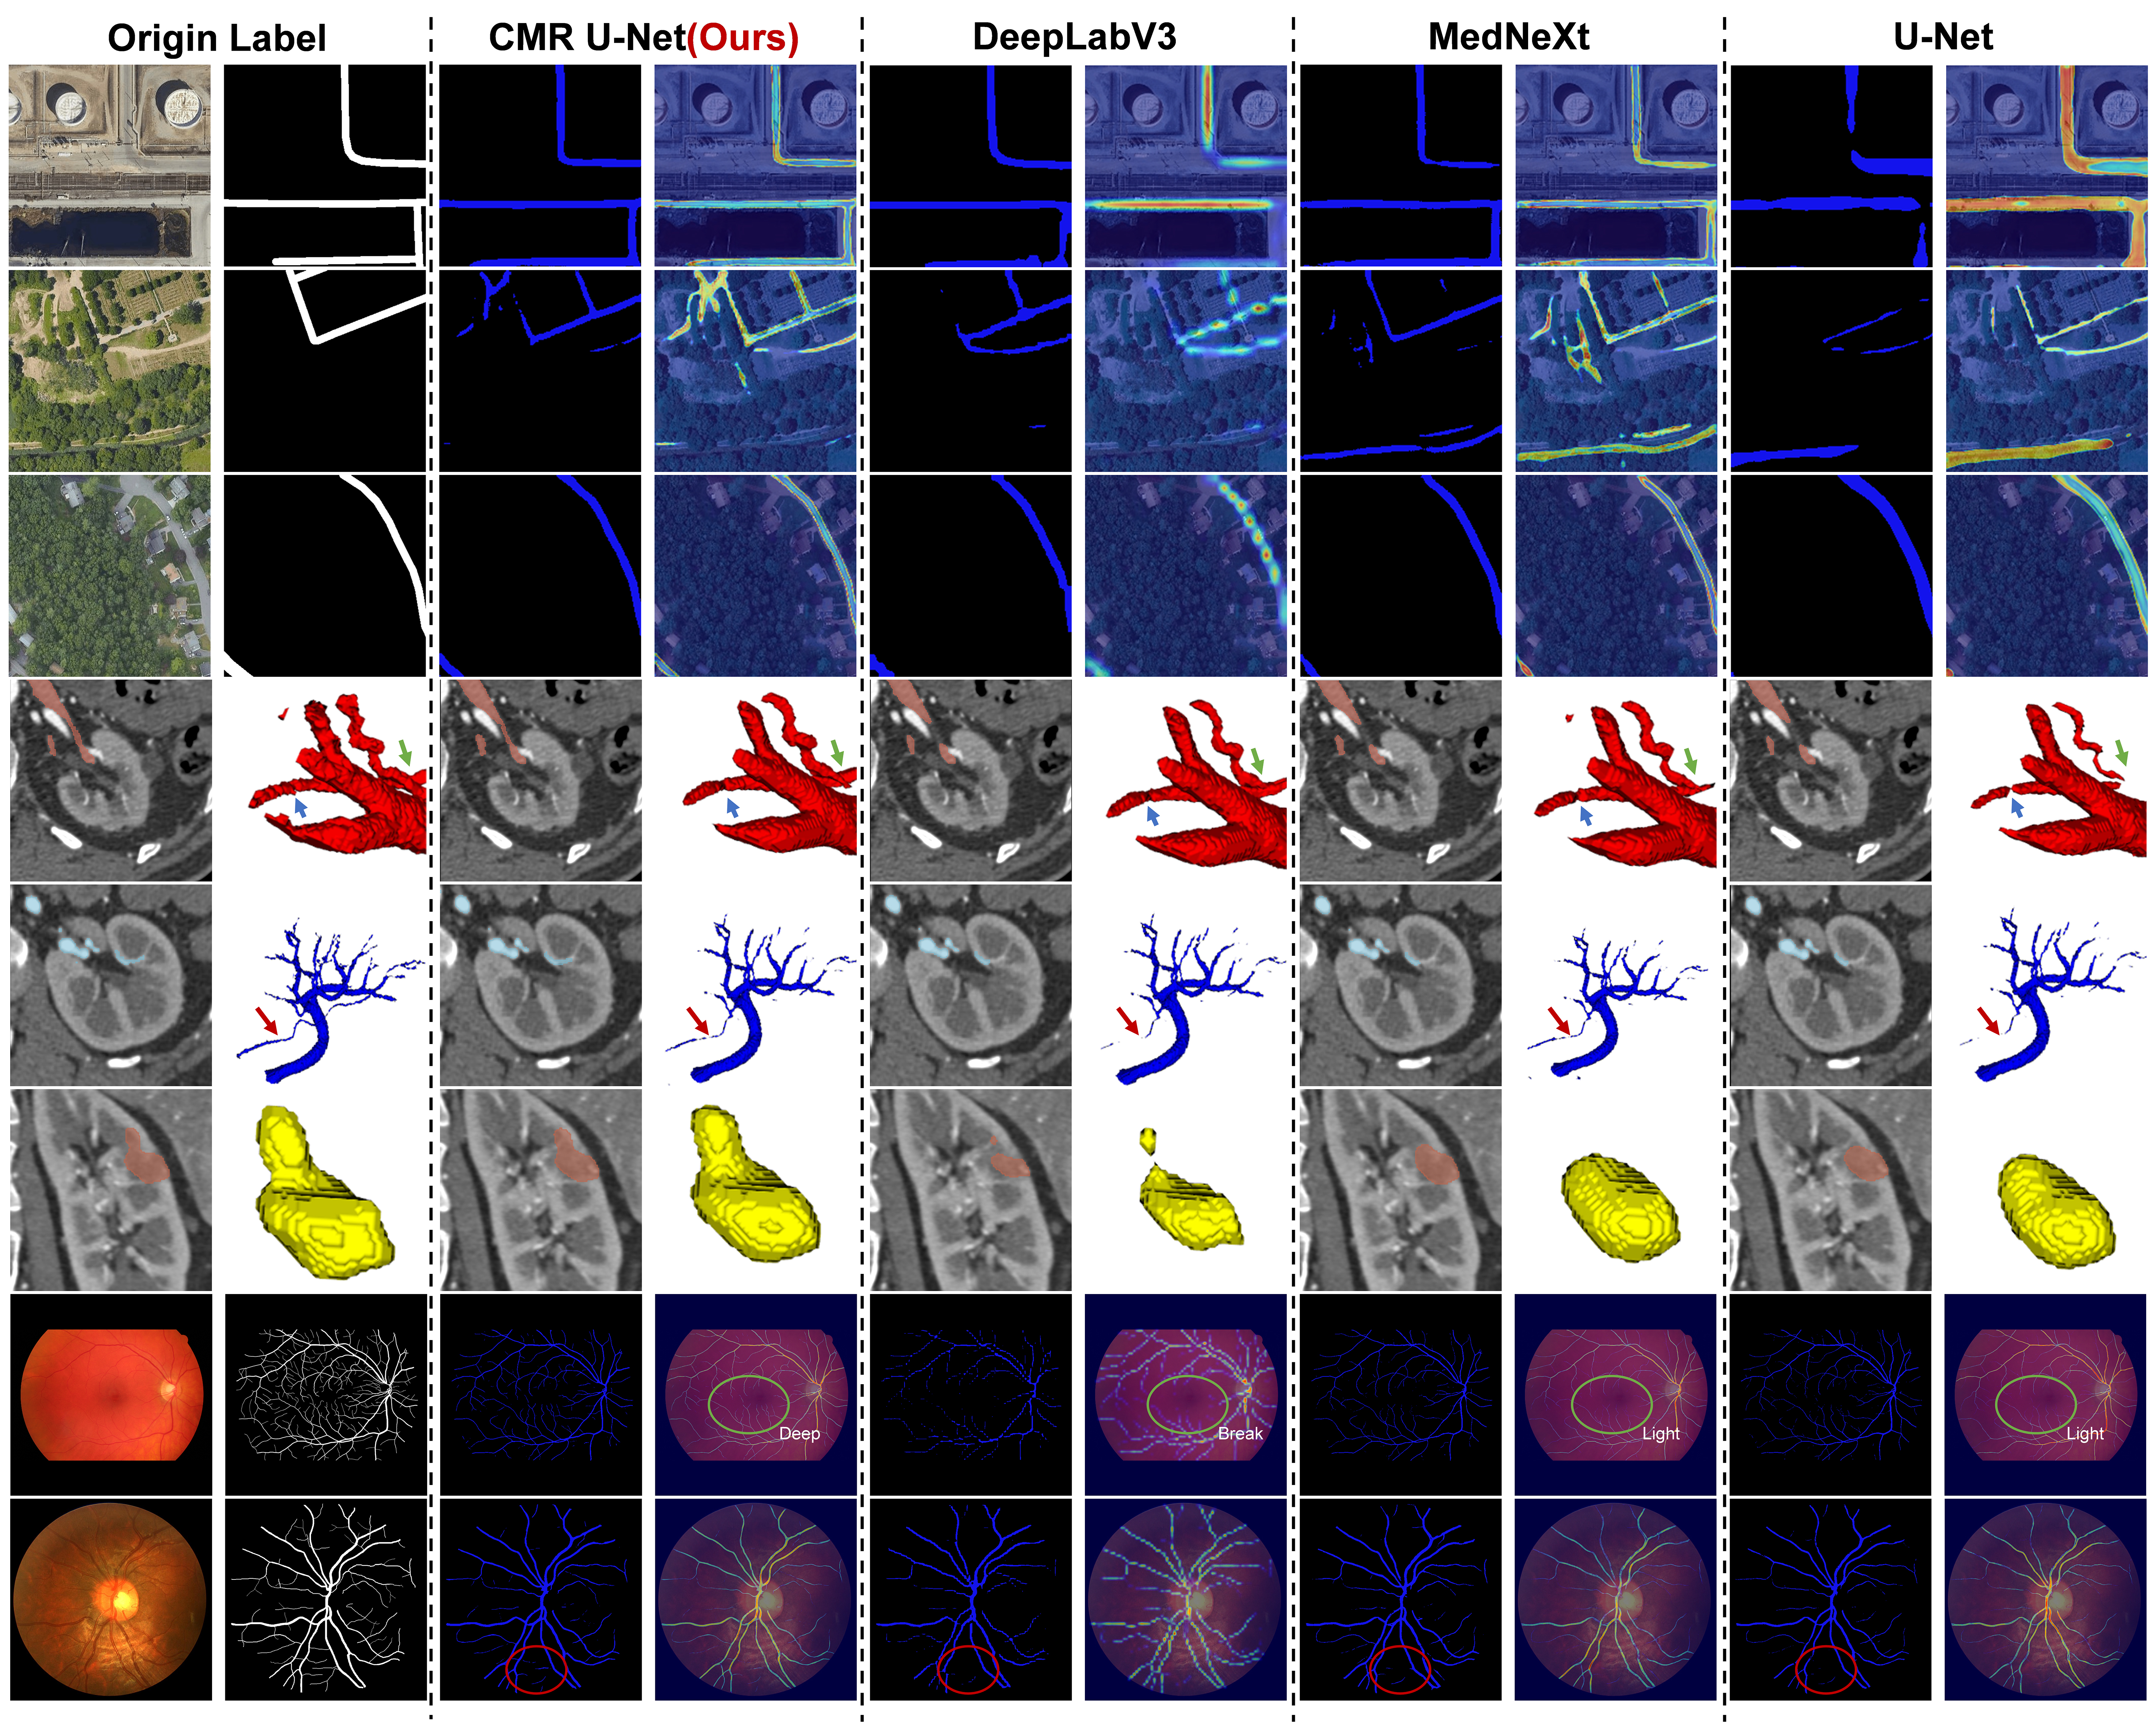

The quantitative analysis results of different networks or losses are shown in Tables 2 and 3, and Figure 9 presents the segmentation results and heatmap effects of varying networks. By comparing the data and segmentation results between these networks, we can see that under the same network training conditions, our proposed CMR U-Net always outperforms in various classification situations and different dimensions. Through the AVD and HD index, it can be seen that its edge recognition ability is stronger than that of other networks.

From the comparison of heat maps in Figure 9, we can more intuitively conclude that the coherence of RCM U-Net is much better. In contrast, DeeplabV3, which uses dilated convolutions, does not maintain continuous heat maps in angled structures. Additionally, MedNeXt and U-Net using traditional convolution are slightly inferior in edge recognition ability and feature extraction ability.